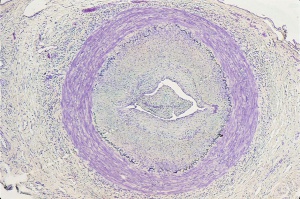

Histopathology

Typical histopathological interpretations of blood vessel biopsies include active arteritis, healed arteritis, arteriosclerosis and atherosclerosis, or normal. Changes in active temporal arteritis include granulomatous inflammation, presence of giant cells, destruction of elastic fibers, splitting and fragmentation of the internal elastic lamina, deposition of calcium salts into the area of the internal elastic lamina, diffuse inflammation of the vessel wall, and ingrowth of capillaries.[6] Healed arteritis encompasses changes including irregular intimal thickening, intimal and medial fibrosis, focal areas of persistent chronic inflammation, confluent loss of the elastic lamina, and medial neovascularization.[7]